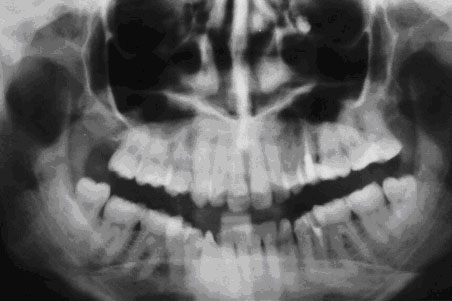

Методы диагностики и лечения

Перед принятием решения о методах лечения необходимо удостовериться в наличии прободения костной перегородки. Это можно сделать, используя миниатюрный зонд, рентген или компьютерную томографию. При проведении рентгенологического исследования обязательно используют контрастное вещество. Полученное изображение позволит определить наличие инородных объектов или сгустков крови в гайморовой пазухе.

Иногда дефект в носовой перегородке бывает настолько древним, что его можно выявить только с помощью медицинских исследований и компьютерной томографии.

Рентген носовых пазух может предоставить значительную помощь. Если на изображении видны темные участки в полости, это может указывать на наличие скопления крови внутри. Также на рентгеновском снимке можно увидеть обломки корней зуба, расположение штифтов и материал, выступающий изнутри канальной пломбы. Для разрешения сомнений может быть полезна рентгенография с применением контрастного вещества.

Одним из недостатков рентгеновских изображений является их плоскость. Получение трехмерного изображения становится возможным при проведении компьютерной томографии. Медицинский специалист проанализирует полученные сканированием данные с помощью специальной программы, осмотрит зуб с различных ракурсов и разработает индивидуальный план лечения.

При таких обстоятельствах результаты носовой пробы и контрольной пробы могут оказаться отрицательными. Положение корня определяется при помощи рентгеновского снимка.